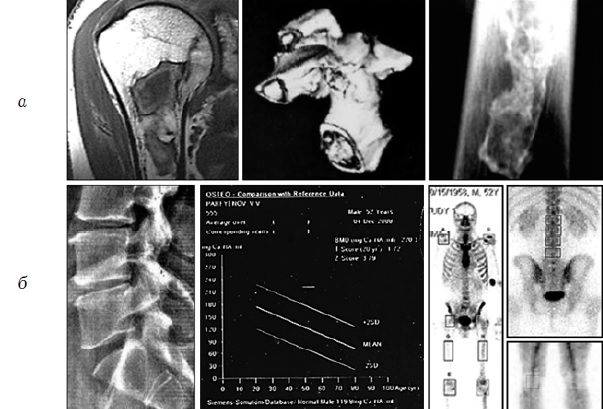

РЕЗУЛЬТАТЫ. У водолазного состава ВМФ отмечены значительные костно-суставные изменения по типу дисбарического остеонекроза, наиболее выраженные у пенсионеров МО – акванавтов.

ОБСУЖДЕНИЕ. Оптимальными методами диагностики дисбарического остеонекроза и «дисбарогенной остеоартропатии» признаны цифровая рентгенография и МРТ. В качестве метода экспресс-диагностики целесообразно использовать инновационные тест-полоски для мочи, позволяющие определить пороговые концентрации маркеров костной резорбции – β-crosslaps и α-crosslaps.

1. Рис. 1. Результаты обследования акванавтов: а – специфические костно-суставные изменения (по данным МРТ, КТ и цифровой рентгенографии); б – дегенеративно-дистрофические процессы в позвоночнике, данные КТ-денситометрии и остеосцинтиграфии (собственные данные) | |